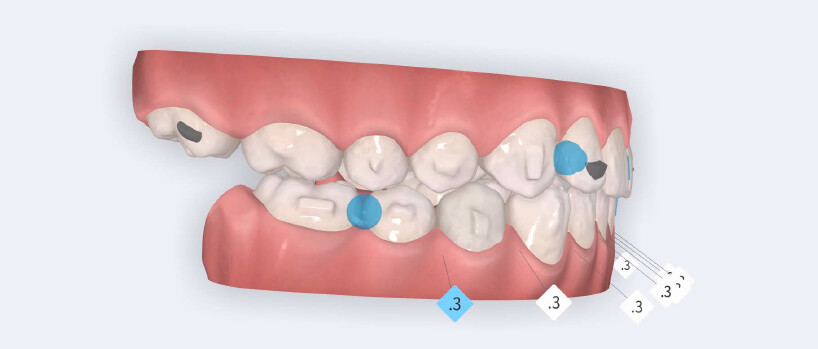

O tratamento seguiu o protocolo de avanço mandibular Angel Aligner A6, com o objetivo principal de alcançar a correção precoce da discrepância sagital enquanto abordava simultaneamente o alinhamento dentário e a coordenação transversal.

O plano de tratamento incluiu:

- Início do avanço mandibular a partir do 4.º alinhador utilizando blocos de avanço mandibular;

- Expansão da arcada para resolver o apinhamento e melhorar a coordenação transversal;

- Redução interproximal seletiva na região anterior mandibular para criar espaço e controlar a inclinação dos incisivos;

- Intrusão programada dos incisivos centrais superiores para reduzir a exposição gengival e corrigir o sorriso gengival;

- Intrusão dos incisivos e caninos mandibulares para nivelar a Curva de Spee;

- Utilização de elásticos de Classe II com Angel Buttons durante a fase de refinamento, para reforçar a mecânica sagital, introduzidos na fase de alinhadores adicionais.

O tratamento foi realizado utilizando alinhadores transparentes Angel Aligner, com estrita observância dos limites biológicos periodontais. Tanto a intrusão dos incisivos superiores quanto a expansão transversal foram cuidadosamente monotorizadas durante todo o processo para evitar qualquer comprometimento periodontal. O avanço mandibular foi iniciado diretamente a partir do 4.º alinhador, utilizando blocos de avanço, eliminando a necessidade de uma fase preliminar de pré-avanço. O paciente encontrava- se no estágio CS3 da maturação das vértebras cervicais, correspondente ao surto de crescimento pubertário, um período biologicamente favorável para o desenvolvimento condilar e adaptação esquelética. Foram utilizados um total de 35 alinhadores com blocos de avanço, seguidos por 10 alinhadores adicionais incorporando elásticos de Classe II nos Angel Buttons para finalizar rotações e alinhamento. Com trocas semanais dos alinhadores, a duração total do tratamento foi de aproximadamente 45 semanas (10 meses), em conformidade com o tempo biológico esperado para a remodelação condilar. Para a intrusão anterior mandibular, o Protocolo Frog combinado com a redução interproximal (IPR) permitiu o nivelamento completo da Curva de Spee.